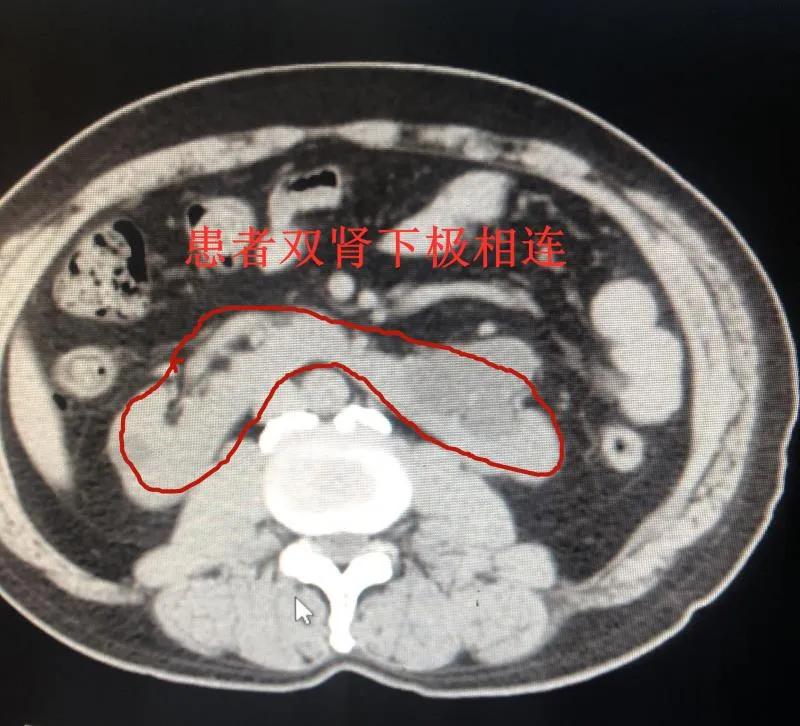

及时完善检查,发现一枚近2公分的结石正好卡在左侧输尿管上段,接诊专家魏世平主任还惊讶地发现,患者邹先生天生肾脏畸形,长了副“马蹄肾”——双肾下极连通,受一侧结石所累,均已出现不同程度的积水、感染,肾功能也出现了异常。